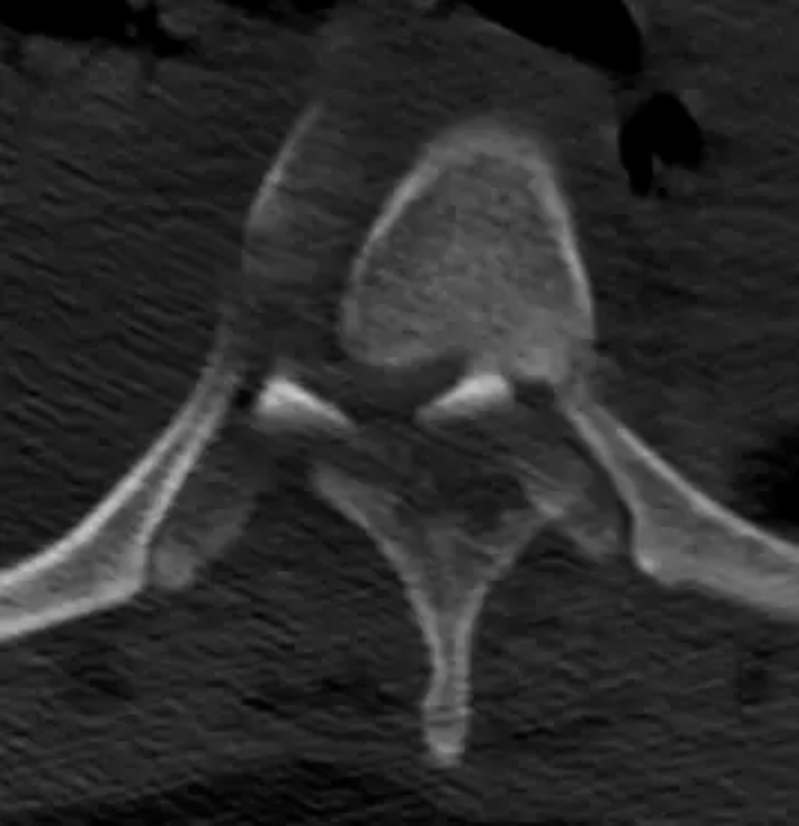

文章配圖

△胸4椎體爆裂性骨折伴脫位。

胸12椎體爆裂性骨折,骨折碎塊壓迫椎管。